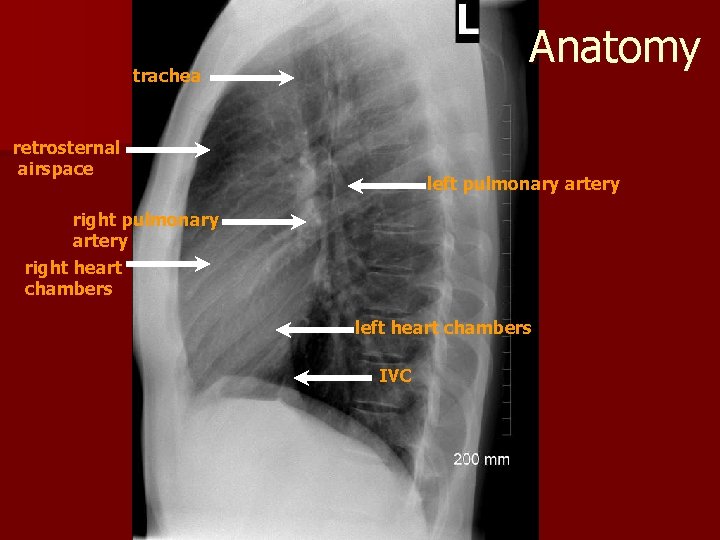

Anatomy trachea retrosternal airspace left pulmonary artery right heart chambers left heart chambers IVC